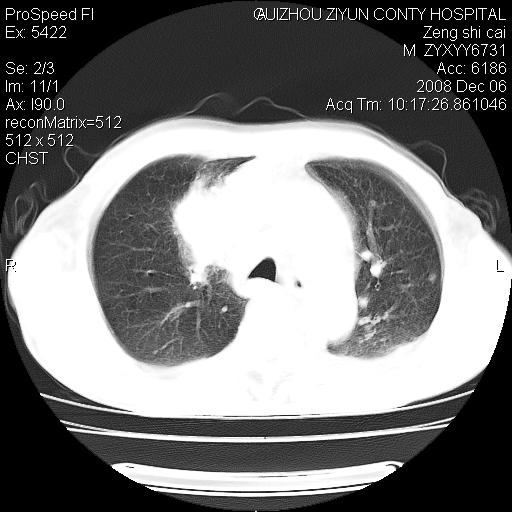

标题: CT16961:M、71岁,咳嗽半年,无血痰;胸片示右肺占位。 [打印本页]

标题: CT16961:M、71岁,咳嗽半年,无血痰;胸片示右肺占位。

1)考虑右肺上叶纵隔型肺癌伴纵隔淋巴结转移。2)心包积液,双侧胸腔积液。

右肺上叶纵隔型肺癌伴纵隔淋巴结转移。心包积液,双侧胸腔积液。